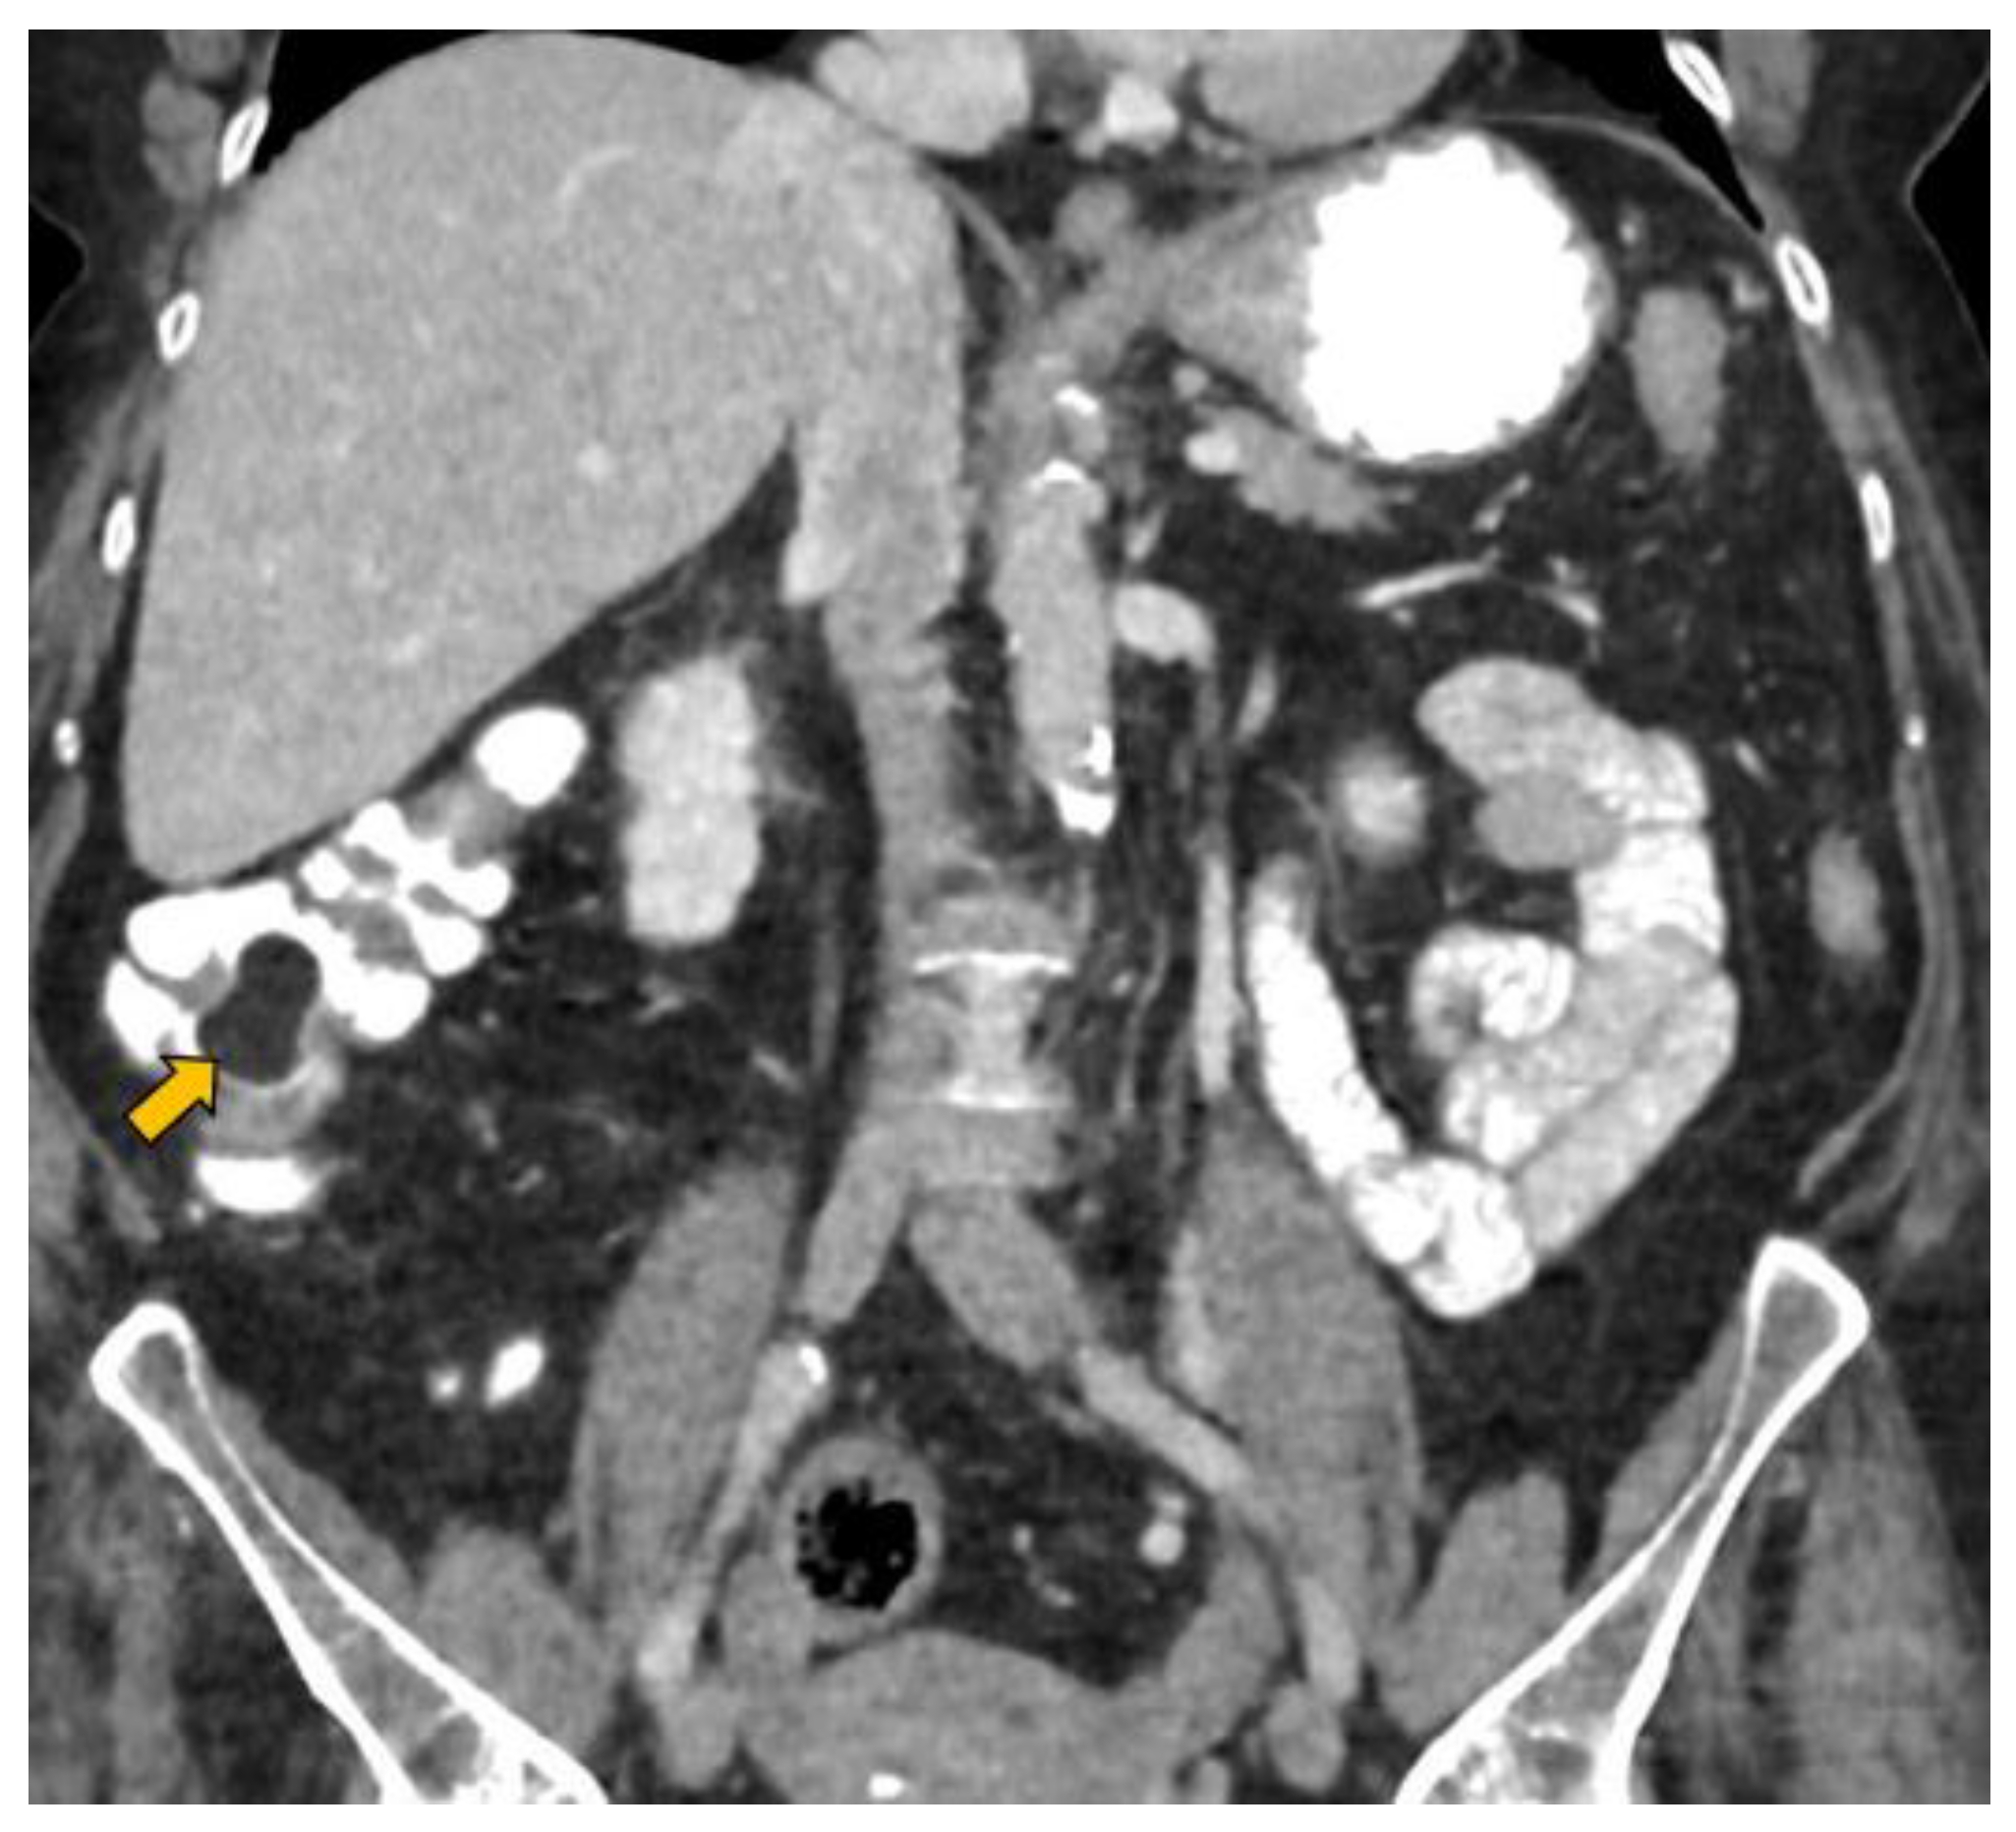

In our case, it was possible to follow up on the lipoma during biannual OCs performed because of her personal history of polyposis. Initially, it was proposed that abdominal-CT scans (Figure 1 and Figure 2) should be performed the year after each OC. This way, the size of the lesion could be monitored, and the degree of local infiltration could be determined. After the first abdominal-CT follow-up, to avoid exposure to radiation, HS (Figure 3) was included as an alternative to abdominal-CT. In the subsequent follow-up, in addition to the biannual OCs, two hydrocolonic ultrasound scans (without cleansing preparation) and one abdominal-CT scan were performed. During the seven years of follow-up, the lipoma remained stable, and the patient remains asymptomatic.

Figure 3.

Hydrocolonic sonography without cleaning preparation. The lipoma between the blue marks (A +, + A) is seen as a hyperechoic image (yellow arrow) projecting into the lumen of the cecum. Faecal remains are observed floating as hyperechoic dotted images in the lumen of the co-lon distended by the serum (blue arrow).

Barium enema findings are nonspecific; it is difficult to differentiate lipomas from malignant lesions using a barium enema [1], and it is not possible to determine the degree of infiltration. Endoscopic or transabdominal ultrasounds show lipomas as hyperechoic images. A hyperechoic image on an endoscopic ultrasound in children is diagnostic of lipoma [1,5]. Although lipomas have been previously diagnosed using transabdominal ultrasound [8], the main limitation of using ultrasounds to study the colon is the presence of intracolonic gas that prevents the visualisation of the colon wall [10,11,12,13,14,15,16,17,18,19,20].

- Lesion size: The sensitivity of HS in the detection of lesions larger than 10 mm is 93% [20]. In our case of a lesion size of 33 mm, it was possible to avoid the discomfort associated with the cleansing preparation. In a recent study, 18 mm lesions were detected with HS without using cleansing preparation [20].

- Lesion location: The segment of the colon in which the lesion is located is an important factor if HS is to be used in follow-up. The rectum is a non-assessable segment. The position of the sigma in the pelvis, the disposition of the transverse colon [20] or the existence of dolichomegalosigma [15,20] are factors that limit the study of these colonic segments. However, the cecum, and ascending and descending colon are more superficial segments and are easier to assess by HS. Our lesion located in the cecum is accessible by HS. However, studying the cecum has peculiarities. First, the presence of faecal remains. Faecal remains frequently accumulate in the right colon [14,15,20]. Faecal remains are observed in the lumen of the colon during retrograde instillation of saline solution and can be moved by using the transducer to compress the abdomen rapidly and lightly [10,11,14,20]. Moving the patient sideways also allows the faecal matter to be displaced, allowing better visualisation. However, they can sometimes be abundant. The concentration of faecal matter can be reduced by increasing the infusion of saline solution [14] if the patient can tolerate it. It is also possible to decrease the faecal concentration by emptying and refilling the colon [20]. Thus, the saline solution together with the faecal remains return to the bag and a new bag of saline solution is used. Second, the ileocecal valve can also be mistaken for a lipoma. The ileocecal valve is seen as a pseudopolyp image projecting into the colon lumen from the ileocecal junction [38] (Figure 4). A lipoma in the cecum may be confused with lipomatosis of the ileocecal valve, which is a more common entity than lipoma [7,36].